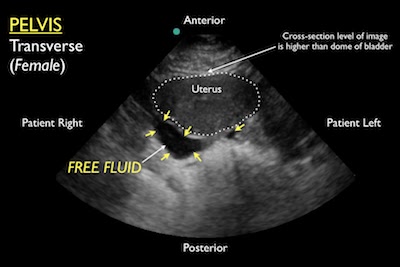

- Component: FAST abdominal views

- Probe: Phased array probe (3.5 – 5 MHz)

- Location: Hepatorenal recess, Splenorenal recess, and bladder

- Finding: Internal blood loss